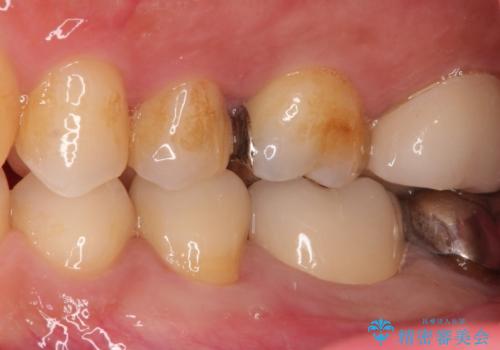

- 金属の詰め物が外れたことを主訴に来院されました。

隣の歯もむし歯を認め、セラミックインレーとセラミッククラウンにて治療を行なっております。

最後方臼歯に関しては治療介入の希望はされませんでした。